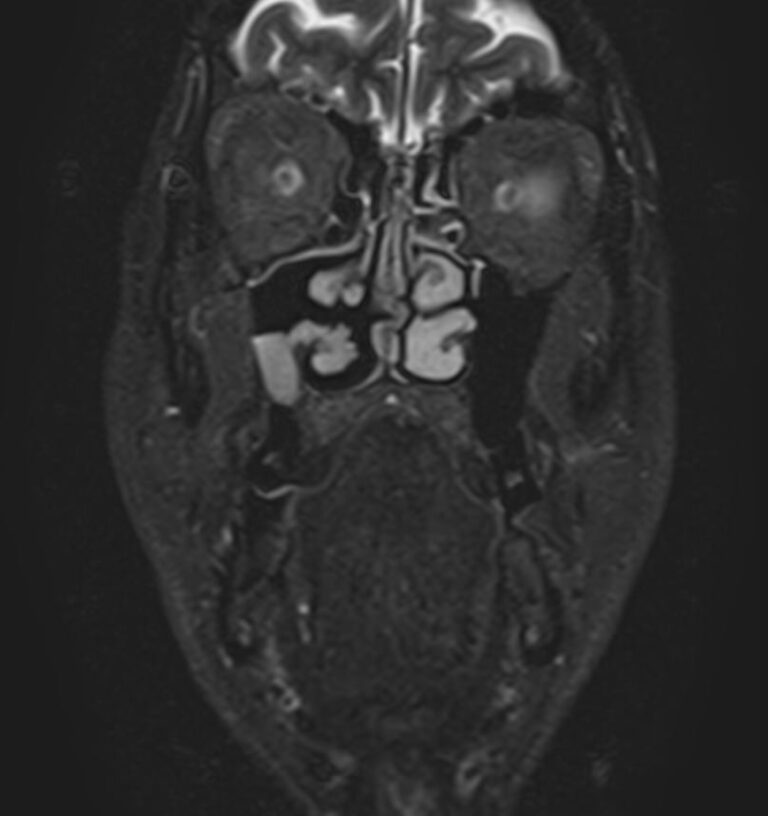

Магнитно-резонансная томография (МРТ) мягких тканей лица – это неинвазивное диагностическое исследование, которое использует магнитное поле и радиоволны для получения детализированных изображений структур мягких тканей в области лица. МРТ мягких тканей лица позволяет визуализировать мышцы, жир, нервы, сосуды и другие мягкотканные структуры, что помогает в диагностике различных заболеваний и патологий, таких как: